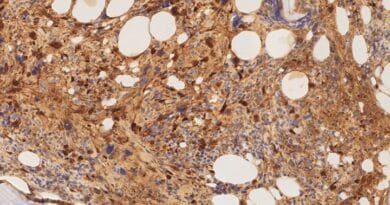

El diagnóstico de la enfermedad de Chagas se realiza en general mediante técnicas serológicas, que en la mayoría de los casos requieren de equipamiento presente en laboratorios centralizados, y de personal entrenado. La obtención de los resultados tarda de 2 a 4 horas. Esta situación limita el diagnóstico en gran parte de la población afectada por la enfermedad, que habita en comunidades rurales, donde los contextos geográficos, socioambientales y culturales (4) restringen el acceso de las personas afectadas a los centros de salud de las grandes ciudades. De allí que la prueba ideal para la detección de la enfermedad de Chagas debería poder realizarse en centros de salud periféricos o en laboratorios móviles a nivel de territorio, con infraestructuras sencillas y con recolección de muestras no invasiva (5).

Los biosensores son (pequeños) dispositivos electrónicos capaces de detectar una molécula de interés, mediante su interacción con un elemento de biorreconocimiento que es parte del sensor. El “acoplamiento” entre la interacción y la señal eléctrica se logra por medio de un transductor que puede ser electroquímico, óptico o magnético, entre otros. El desarrollo de biosensores tiene como objetivo la detección de sustancias de manera sencilla y sin utilizar equipamiento grande, tal es el caso del sensor de glucosa electroquímico que se utiliza en la tecnología del páncreas artificial en algunos pacientes con diabetes (6).

Desde 2013 en el grupo SuNaBi (Superficies Nanoestructuradas para Biosensado y estudio de interacciones Biomoleculares) del Instituto de Investigaciones Fisicoquímicas Teóricas y Aplicadas (INIFTA), trabajamos en el desarrollo de biosensores para el diagnóstico de enfermedad de Chagas. Como grupo especializado en química de superficies, nos encargamos de estudiar distintas estrategias de inmovilización de proteínas de Trypanosoma cruzi en sensores de oro de diversa naturaleza, desde DVDs recubiertos con oro (7) hasta minúsculos electrodos serigrafiados montados en una placa cerámica del tamaño de una SIM de celular (8). Trabajamos en colaboración con centros de salud de referencia de nuestra región, como el Instituto Nacional de Parasitología (INP- Fatala Chabén) (9) y el Hospital de Alta Complejidad “El Cruce” y con grupos de investigación internacionales de la Universidad de Bath (Inglaterra) (10) y de la Universidad de Padua (Italia), con el objetivo de proponer biosensores para el diagnóstico de Chagas que cada vez se acerquen más a formatos portátiles.